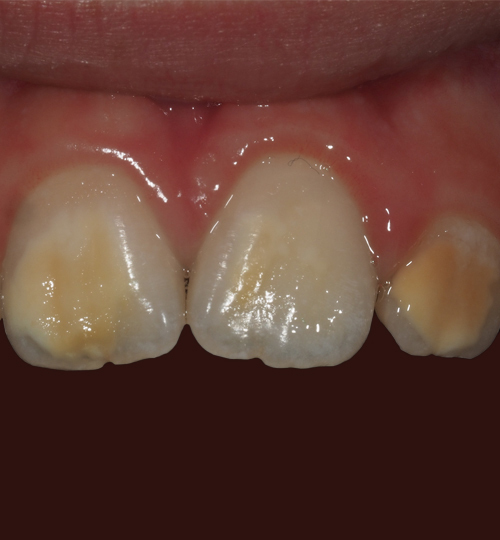

La MIH est une anomalie de la structure de l’émail se traduisant par un défaut qualitatif de l’émail sur au moins une des quatre premières molaires permanentes, associé ou non à une atteinte d’une ou plusieurs incisives permanentes (fig. 1).1 Les autres dents permanentes sont plus rarement atteintes. On peut également retrouver une atteinte similaire au niveau des deuxièmes molaires temporaires, appelée alors HSPM (hypomineralised second primary molar). Un enfant atteint de HSPM a cinq fois plus de risque d’être atteint de MIH en dentition permanente.

Le diagnostic repose sur l’observation clinique : des opacités (taches) blanches, beiges ou brunes de taille variable sont présentes et visibles sur les dents atteintes (fig. 1, 2 et 3). Les opacités, bien démarquées, sont présentes dès l’éruption de la dent et leur taille ne se modifie pas dans le temps. Cependant, l’émail étant plus fragile, des fractures amélaires post-éruptives sont observées, entraînant des pertes de substance surtout au niveau des molaires qui sont soumises aux forces de mastication. L’atteinte est asymétrique, c’est-à-dire que pour un même patient sa sévérité peut varier d’une dent à l’autre, allant d’une absence d’atteinte à une perte de substance importante, en passant par une dyschromie discrète. Si une tache est observée sur une incisive permanente, il est important d’examiner les molaires permanentes. Le médecin généraliste doit alors évoquer une anomalie de structure dentaire et orienter le patient vers un chirurgien-dentiste. Celui-ci confirmera le diagnostic de MIH ou établira un autre diagnostic. Les diagnostics différentiels sont :